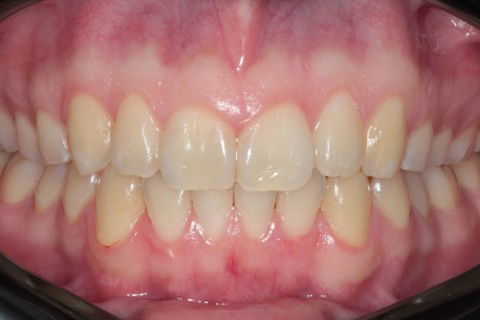

Final Fontal

1º Passo: Planejamento Digital com software Clincheck;

2º Passo: Confecção de 36 alinhadores personalizados conforme planejamento;

3º Passo: Evolução do tratamento que teve duração total de 18 meses, com a utilização de elástico de Classe II;

4º Passo: Checklist Oclusal + Fotografias finais.

Obs: Nesse caso não foi utilizado alinhadores adcionais para refinamento.